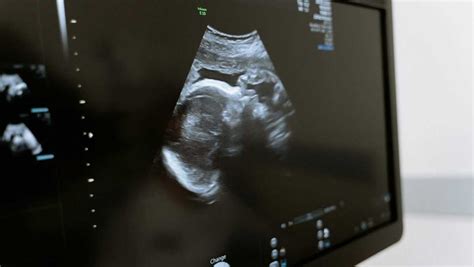

3D/4D ultrazvuk predstavuje pre budúcich rodičov zážitok vidieť svoje dieťa prenatálne pred narodením. Na rozdiel od tradičného 2D ultrazvuku, ktorý zobrazuje plôšky a rezy, 3D ultrazvuk vytvára trojrozmerné obrazy, ktoré umožňujú detailnejšie preskúmanie vzhľadu dieťaťa. 4D ultrazvuk ide ešte o krok ďalej, keďže zobrazuje tieto trojrozmerné obrazy v reálnom čase, čo umožňuje sledovať pohyby plodu, ako je napríklad zívanie, cmúľanie palca alebo úsmev.

3D/4D ultrazvukové vyšetrenie je možné realizovať v priebehu celej gravidity, avšak optimálne obdobie je medzi 22. až 26. týždňom tehotenstva. V tomto období je plod dostatočne vyvinutý, aby bolo možné zobraziť jeho tvár a končatiny, ale zároveň je stále dostatok plodovej vody, ktorá zabezpečuje kvalitné zobrazenie.

Okrem emocionálneho aspektu má 3D/4D ultrazvuk aj významný diagnostický prínos. Tento typ ultrazvukového zobrazenia pomáha spresniť diagnózu s posúdením niektorých vývojových anomálií plodu. Umožňuje sledovať detaily tváre, končatín a celkovú anatómiu plodu, čo môže viesť k včasnej identifikácii prípadných problémov a následnému plánovaniu ďalšej starostlivosti.